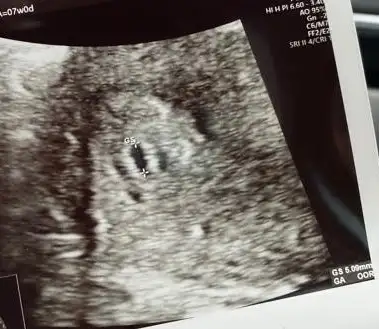

Merhaba, bizim kese görüntülerimiz hafta hafta bu şekilde şu an 7+1 deyiz, yorumlara bakınca kafam karıştı ne olabilir acaba? :)))

• WhatsApp Image 2023-06-21 at 16.12.57 (1).webp

WhatsApp Image 2023-06-21 at 16.12.57 (1).webp

15,5 KB · Görüntüleme: 623